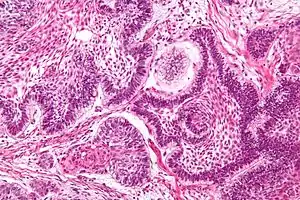

| Micrograph of an ameloblastoma showing the characteristic palisading and stellate reticulum. H&E stain. | |

Follicular

The most common follicular type has an outer arrangement of columnar or palisaded ameloblasts-like cells and inner zone of triangular shaped cells resembling stellate reticulum from the bell stage of tooth development.[8]

Plexiform

The plexiform type has epithelium that proliferates in a "Fish Net Pattern". The plexiform ameloblastoma shows epithelium proliferating in a 'cord like fashion', hence the name 'plexiform'. There are layers of cells in between the proliferating epithelium with well-formed desmosomal junctions, simulating spindle cell layers. The ameloblasts cells can be less prominent.[8]